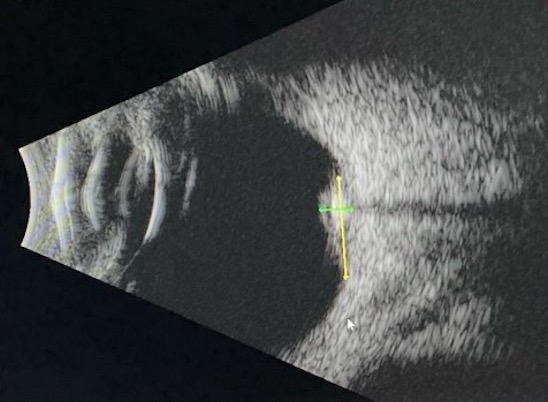

B scan of retinocytoma shows high internal reflectivity with shadowing from intralesional calcifications.

| current | 07:14, July 31, 2025 | 548 × 402 (54 KB) | Kendra.Hong (talk | contribs) | B scan of retinocytoma shows high internal reflectivity with shadowing from intralesional calcifications. Dimensions are 2.1 mm (height) x 7.0 mm (base). |